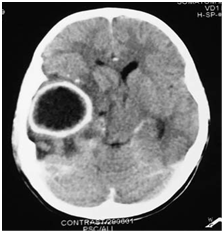

In cases of brain abscesses, although the MRI gives better detail regarding the abscess itself, a CT scan gives valuable information about bony erosion of the mastoid, and can help in determining the cause of the abscess and the most appropriate treatment options (Figure 6–9).

Figure 9 CT scan showing cerebellar abscess on the right side.